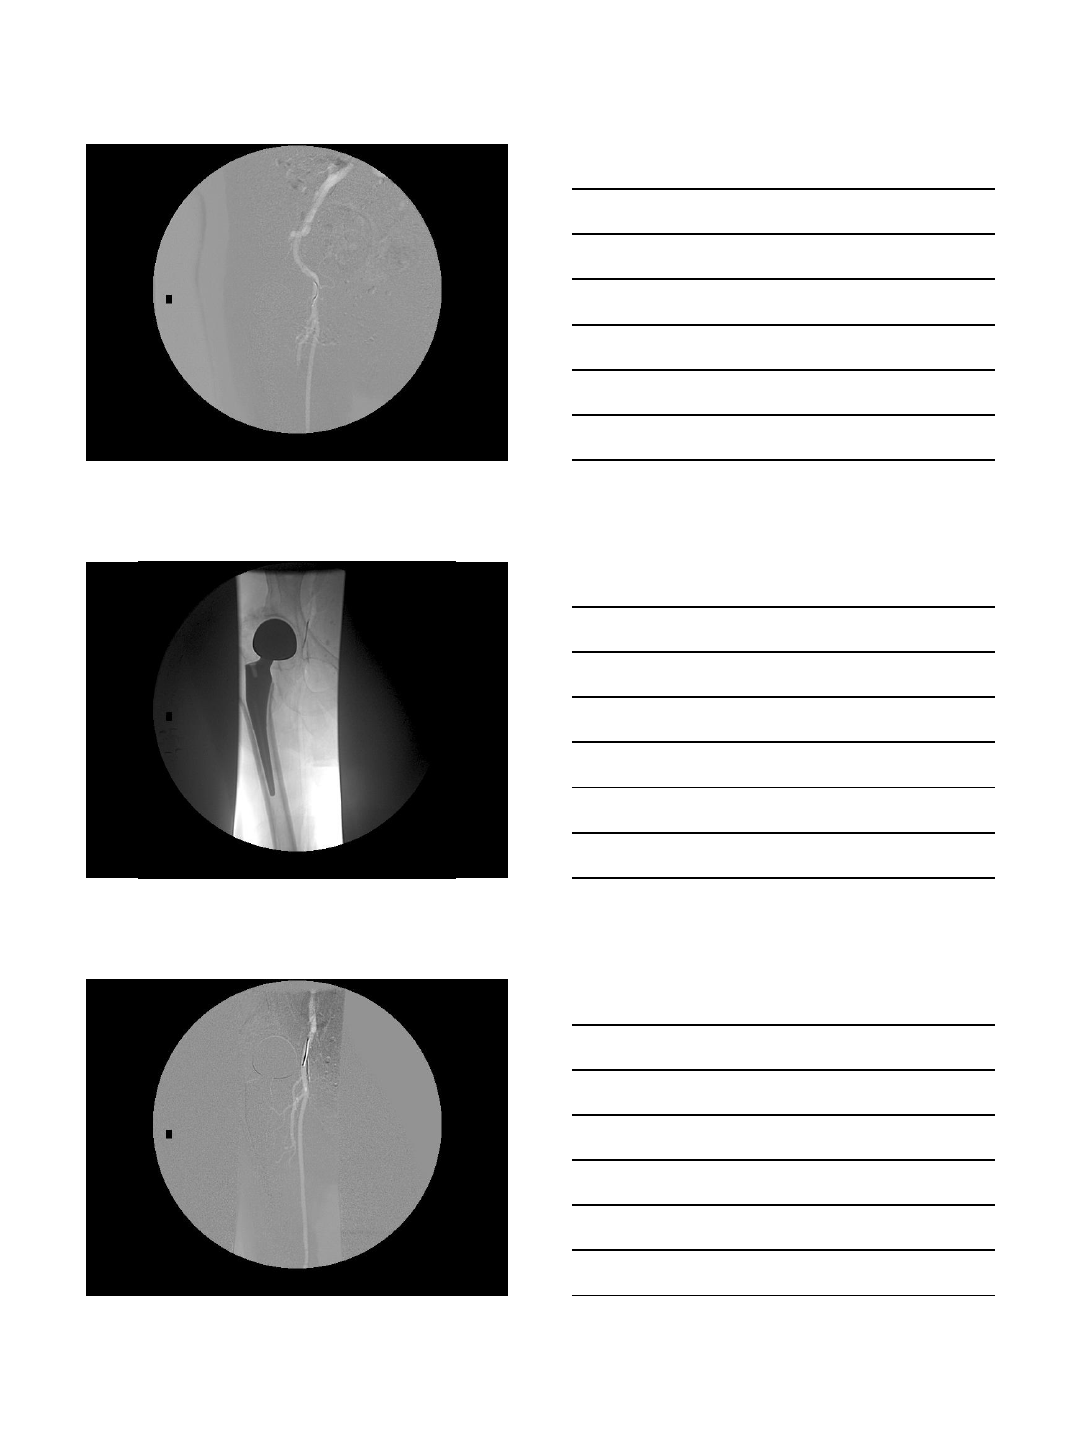

Absorption of CO2 bubble in RA

after injection of 5 cc of CO2

Non-absorption of air bubble in

RA after injection of 5 cc of air

Injection of 30 cc of CO2 into L

external iliac artery via a 3F dilator